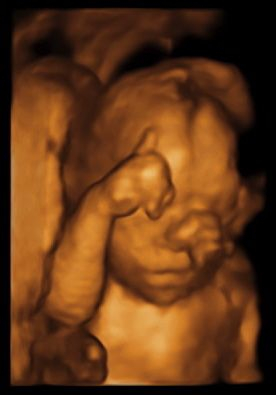

But in the meantime....LOOK AT THAT FACE!!! 😍